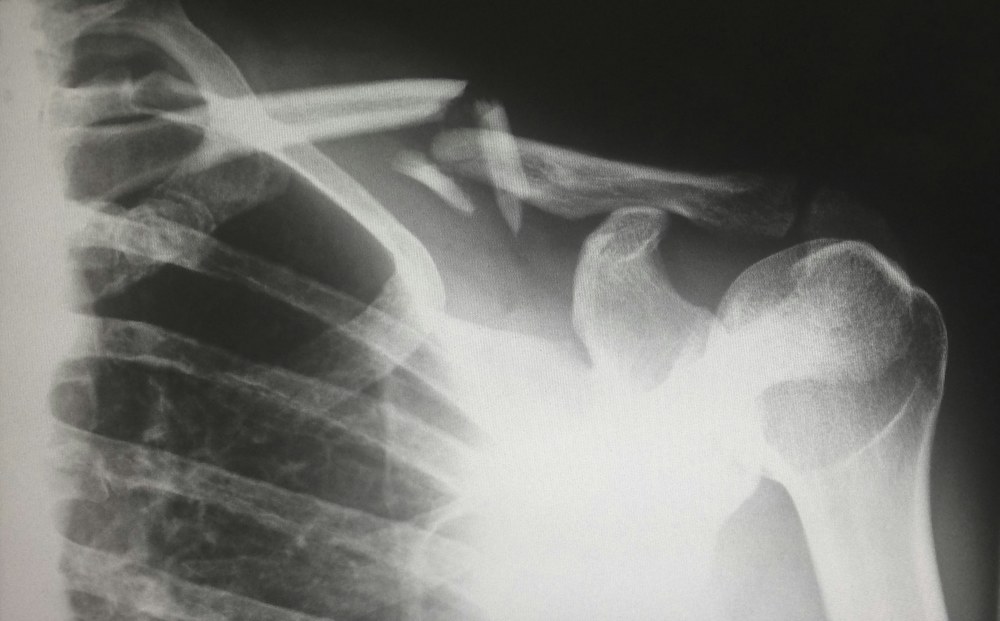

Фахівці Medical Plaza розповіли, коли ендопротезування розглядають як шлях повернення рухливості

Біль у суглобі рідко приходить урочисто. Спочатку він просто заважає довше пройтися, потім псує сон, […]